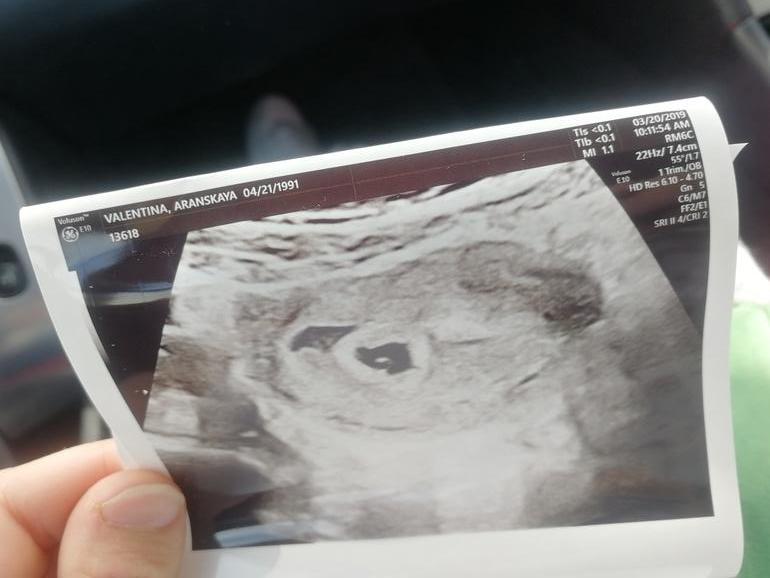

5 недель

Беременность- 1 триместр ( только до 10 недель)Ходила ну первый приём к доктору. Нашей бусинке 5 недель, сб ещё нет. Нашли малявку через живот, доктор сказала, что почти все хорошо. Есть гематома, нужно принимать прогестерон. В общем, мы могли бы её и так оставить (мы с мужем хотели обойтись без поддержки в 1 триместре), но мне скоро начинать пить кардиомагнил, и тут никаких гематом быть не должно.